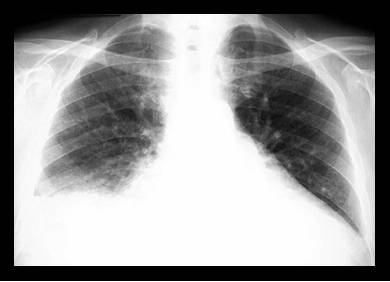

Radiografia pulmonara evidentiaza cardiomegalia ( creste indicele cardiotoracic) si semne de redistributie a circulatiei pulmonare - edemul interstitial si alveolar, hidrotoraxul.

-Radiografia cord-pulmon - cordul poate fi normal sau mult dilatat, congestia pulmonara fiind prezenta la cazurile fulminante.